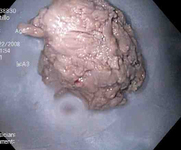

Fotografia endoscópica de uma impactação de alimentos na porção inferior do esôfago com um anel mucoso concêntrico evidente sugerindo uma esofagite eosinofílica

Do acervo de Juan Carlos Munoz